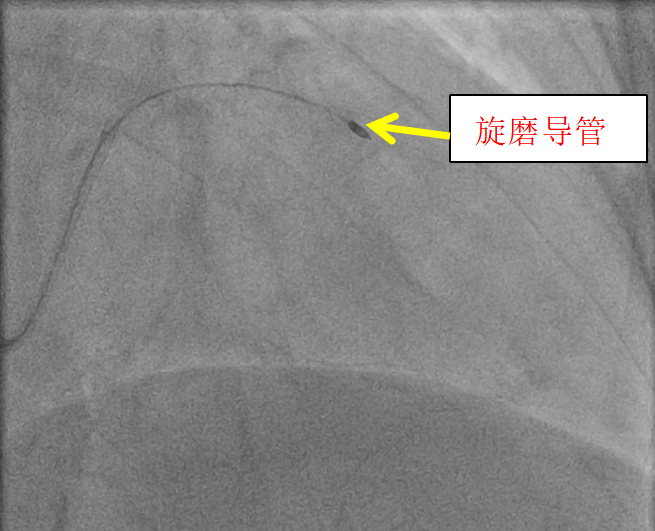

术中,常规使用的球囊无法通过病变处,为有效解除冠脉狭窄,遂立即决定采用全新一代ROTAPRO™旋磨介入治疗系统为黄女士开通生命通道。

旋磨处理过程

戴闽教授强调冠状动脉钙化病变被称为“介入领域的硬骨头”,血管内斑块坚硬如石,血管管腔狭窄严重且解剖结构复杂,如同在“布满礁石的狭窄河道”中开辟道路。操作中,术者需要精准操控旋磨头以超高速旋转(每分钟数16万转),既要将钙化斑块“磨碎”成微米级颗粒,又要绝对避开血管壁,稍有偏差就可能引发血管穿孔、夹层等致命风险,对术者的操作精度、手感和应急反应提出极致考验。

而正是这样的“不可能任务”,在戴教授手中化为“精准突破”。手术全程,戴教授凭借十余年积累的丰富经验和扎实的介入功底,始终保持稳定的手眼配合,在影像引导下精准调整旋磨头的角度与转速,像“显微外科医生绣花”般细致操作。面对术中血管压力的细微波动,戴教授迅速判断、果断应对,最终顺利完成旋磨并植入支架,让原本堵塞的血管重新恢复通畅。